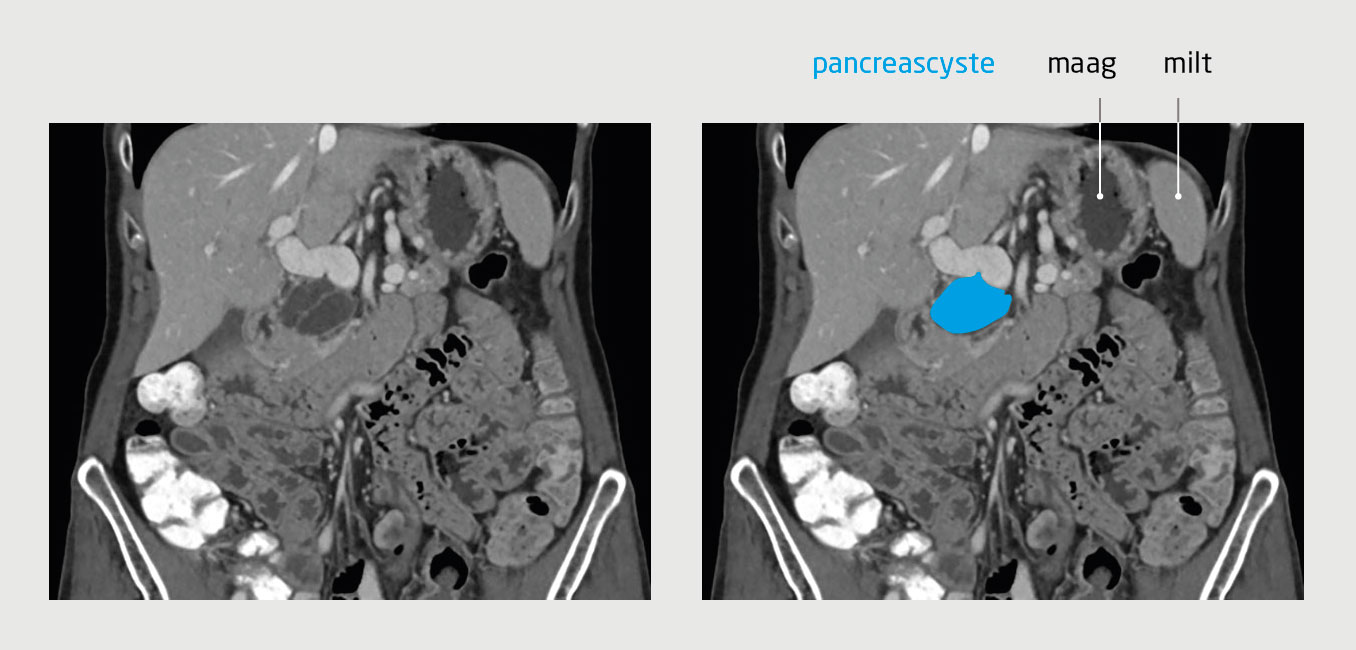

Patiënt A, een 77-jarige, actieve, fitte vrouw met hypertensie en claustrofobie, wordt vanwege buikpijn door de huisarts naar het ziekenhuis verwezen voor echografie van het abdomen. Daarbij wordt een pancreascyste vastgesteld. Aanvullend CT-onderzoek van het abdomen toont een cyste met een diameter van 46 mm en septaties, maar geeft geen duidelijkheid over het type cyste (figuur 1). Patiënt vertelt ons dat zij last heeft van een zeurende pijn boven in de buik. Haar eetlust is goed, de ontlasting is onveranderd en het gewicht is stabiel. De familieanamnese is negatief voor pancreasproblemen.

Figuur 1 | Pancreascyste met septaties bij patiënt A

Coronale CT-opname van het abdomen tijdens de portaal veneuze fase van een 77-jarige vrouw, waarop een pancreascyste te zien is met een diameter van 46 mm en septaties.